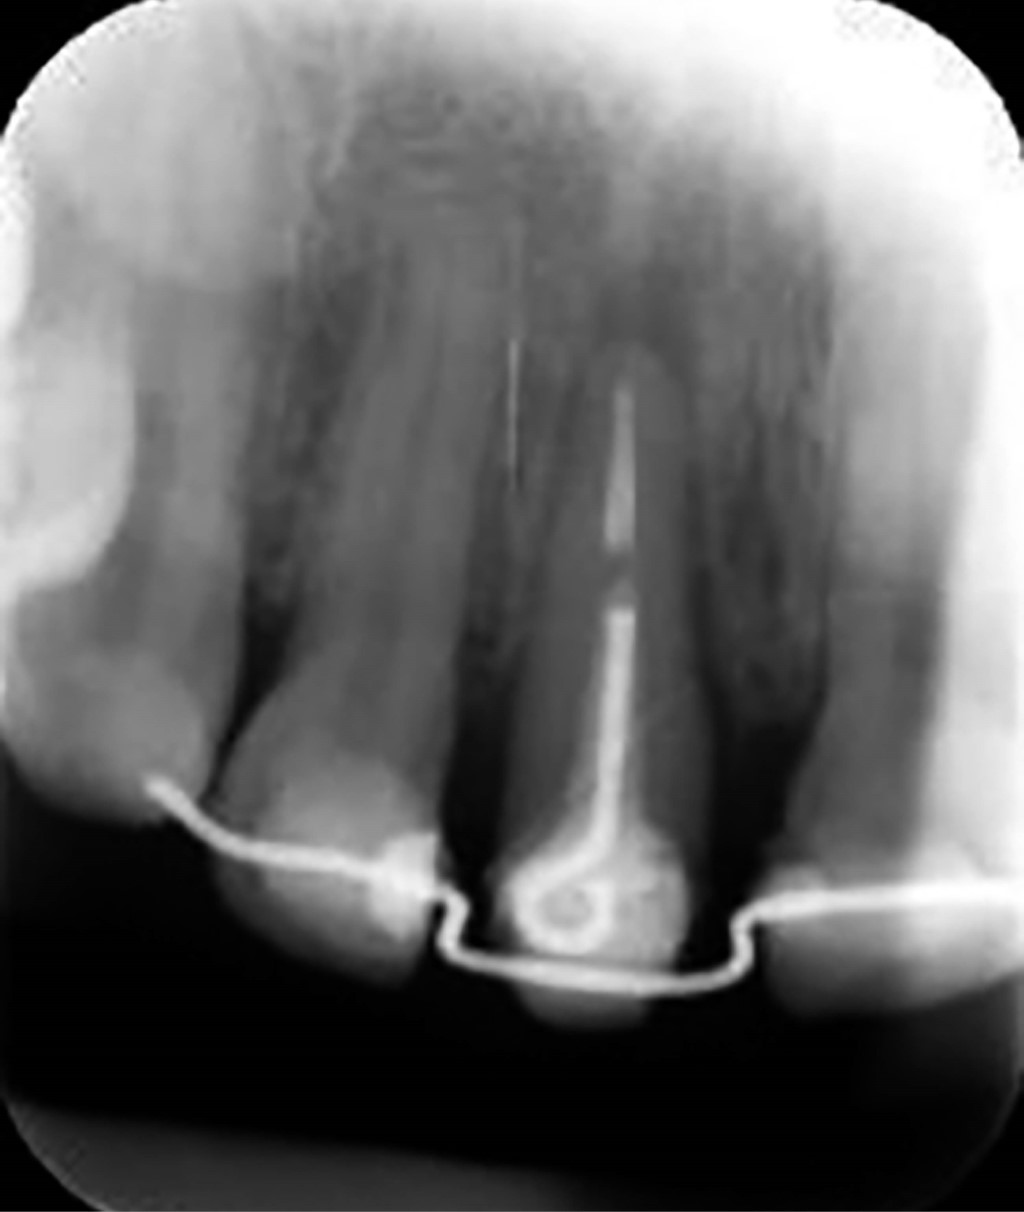

Paciente femenino de 26 años de edad, ASA I, acude a la clínica de la Universidad AME (especialidad en periodoncia) con motivo de consulta "Quiero una solución para mi diente". Como resultado de la exploración intraoral presenta fractura coronal del órgano 1.1, observándose como resto radicular, y pigmentación melánica fisiológica en la mucosa del área anterosuperior. En la examinación periodontal muestra un ancho de encía queratinizada de 5 a 8 mm, profundidades al sondeo de 1 a 2 mm, no se observa pérdida de inserción clínica. Radiográficamente se observa una raíz larga del órgano dental 1.1 con un área radiopaca en el interior correspondiente a un tratamiento de conductos previo (Figura 1). El diagnóstico periodontal es enfermedad gingival no inducida por biopelícula causada por lesión traumática y pigmentación gingival de etiología fisiológica, con un pronóstico bueno en los órganos 13, 12, 21, 22, 23 y sin esperanza en 1.1.8

Una vez concluido este proceso, se realizó el cambio de cadenas elastoméricas de segunda generación con un periodo semanal. Al cumplir la tercera semana, se observó el contacto del loop con el alambre de ortodoncia, cumpliendo con el objetivo de los 3 mm de extrusión necesarios (Figura 3). Se tomó una radiografía de control donde se pudo constatar la migración en sentido coronal de dicho órgano dentario (Figura 4).

Se efectuaron citas de control posteriores al presente procedimiento. Una vez transcurrida la primera semana se descartó presencia de signos de infección o inflamación y se refirió al departamento de restauradora para la colocación del núcleo y provisional (Figura 6). A los siete meses, se tomó una radiografía periapical y se comparó radiografías del proceso de antes, durante (a las tres semanas) y después (a los siete meses). Se observó la aposición o formación del tejido óseo en el área del ápice (Figura 7).

Figura 1

Figura 4